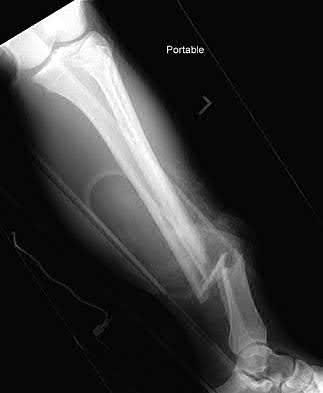

A 25-year-old female is involved in a motor vehicle collision. She presents with the isolated injury seen in Figures A through D. Her leg is swollen but her skin is intact. She has no clinical signs of compartment syndrome. Which of the following treatment options will allow for maintenance of fracture alignment and minimize the risk of soft tissue complications?

The patient presents with a closed distal third metaphyseal-diaphyseal distal tibia fracture with simple intra-articular extension. Immediate intramedullary nailing along with percutaneous fixation of the articular component provides appropriate restoration of length, rotation and alignment and minimizes the risk of wound complication.

Displaced distal third tibia fractures may be associated with simple intraarticular extension. Operative treatment of intra-articular distal tibia fractures has historically been performed with open reduction and internal fixation. Early open reduction and plate fixation of pilon fractures has been associated with high rates of infection and wound complication. In select patterns with simple articular extension, percutaneous screw fixation and medullary nailing may provide appropriate reduction with minimal soft-tissue risk.

Figures A and B demonstrate a distal third tibial shaft fracture with simple intra-articular extension. The axial and coronal CT cuts in Figures C and D further clarify the articular injury. Illustrations A and B demonstrate a comminuted distal third tibial fracture with simple intra-articular extension. Illustrations C and D are fluoroscopic images of the same injury after intramedullary nailing and percutaneous fixation of the articular component.